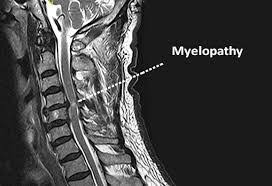

Όγκοι σπονδυλικής στήλης

Οι όγκοι της σπονδυλικής στήλης είναι συνηθέστερα όγκοι σπονδυλικών σωμάτων που αφορούν μεταστάσεις από κακοήθειες άλλων οργάνων. Επίσης δεύτεροι συχνότεροι όγκοι είναι καλοήθεις όγκοι μέσα στην σκληρά μήνιγγα (εξωμυελικοί), όπως...